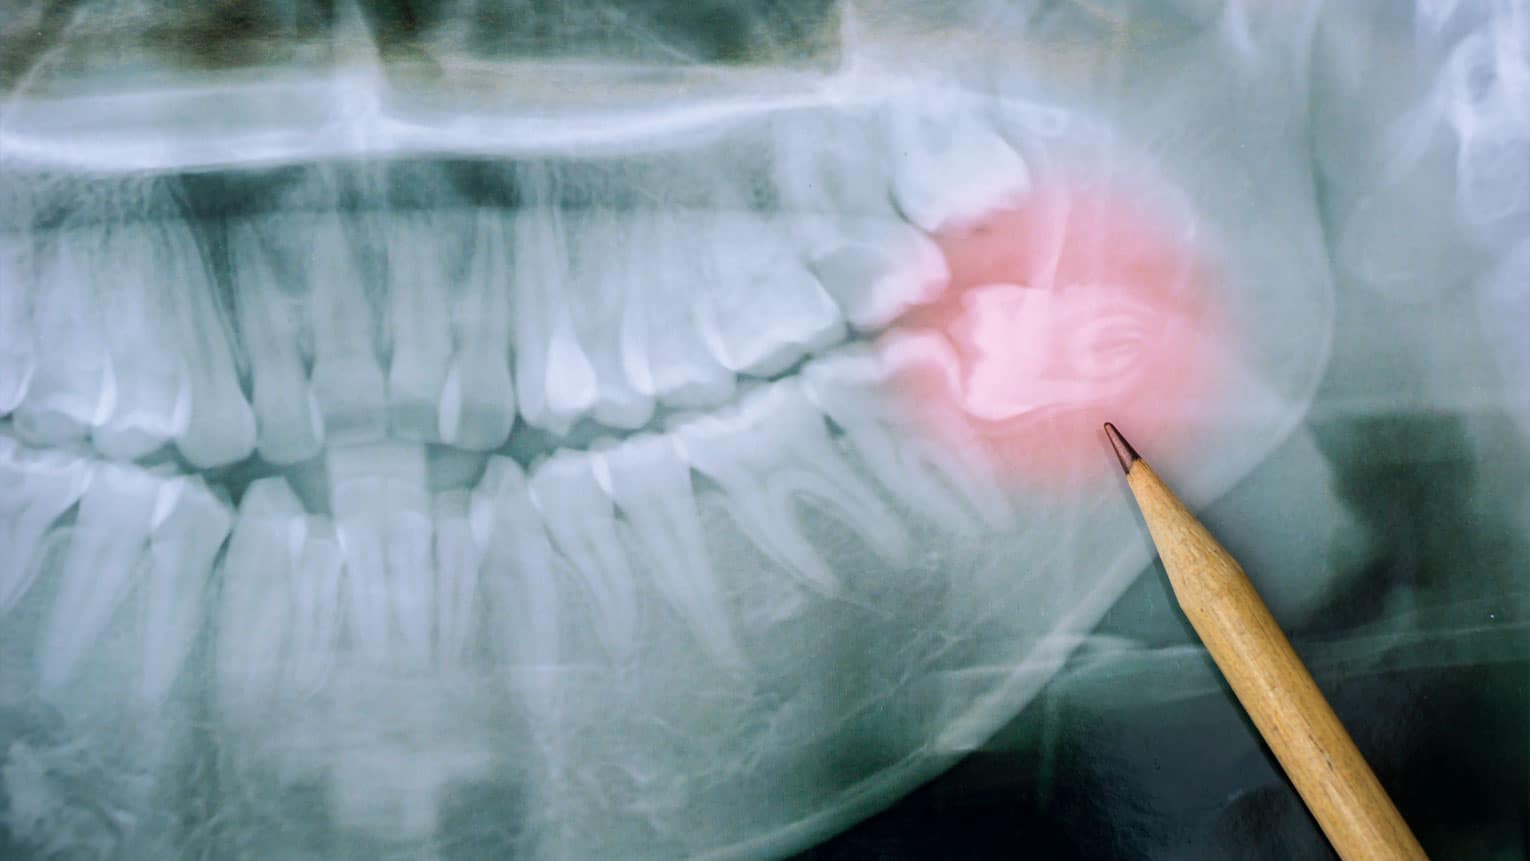

Wisdom Teeth: Why Do We Have Them and When Should They Go?

Wisdom teeth are the third molars that typically emerge during late adolescence or early adulthood. Unfortunately, they often lead to oral health issues, prompting the removal of approximately 10 million wisdom teeth each year in the U.S. Discover why these teeth can…